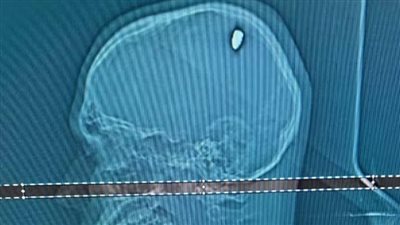

رأى شاب برازيلي نفسه محظوظا لبقائه على قيد الحياة لمدة 4 أيام، بينما استقرت رصاصة من عيار 9 ملم في رأسه.